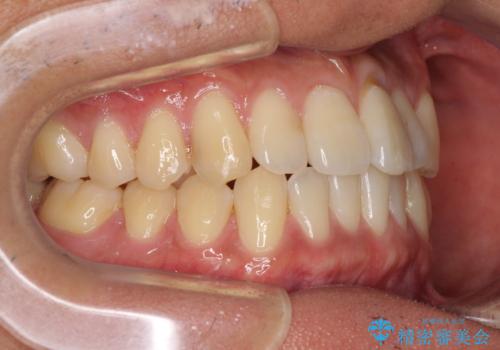

気になる前歯のデコボコをインビザラインで解消

- 前歯のデコボコを気にして来院された患者様です。

主に下顎歯列全体の後方移動とIPR(歯と歯の間を削る)によってデコボコが解消するように設計し、インビザラインにより治療を行うこととしました。

インビザライン矯正特有の、治療後半で前歯のみが強く接触する症状が発現し、咬み合わせ改善に期間を要することとなりました。